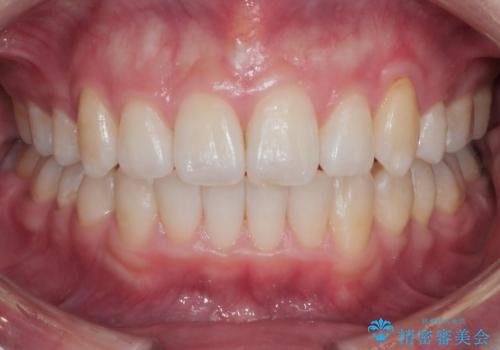

八重歯でがたつきは重度でしたが、きれいな歯並びにすることができました。

がたつきだけでなく、奥歯の噛み合わせのずれの調整もしっかり行いました。

奥歯のずれの調整は時間がかかりますが、矯正後の歯並びの安定度が向上します。

歯並びがきれいになることで、虫歯予防や歯周病予防にもつながります。